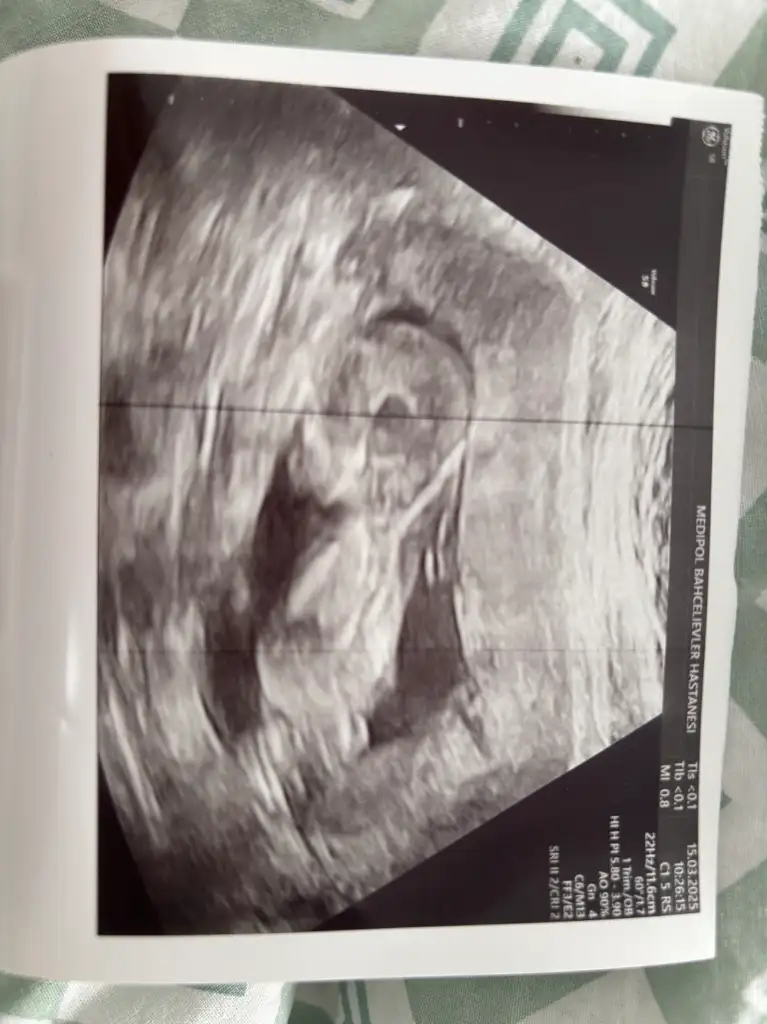

Kızlar 13+5 deyim anlayan arkadaşlar bakabilir mi ? Doktor kıza benzetti çıkıntı olmadığı için, erkek olsaydı çıkıntının oluşmuş olması mı gerekiyordu bu haftada